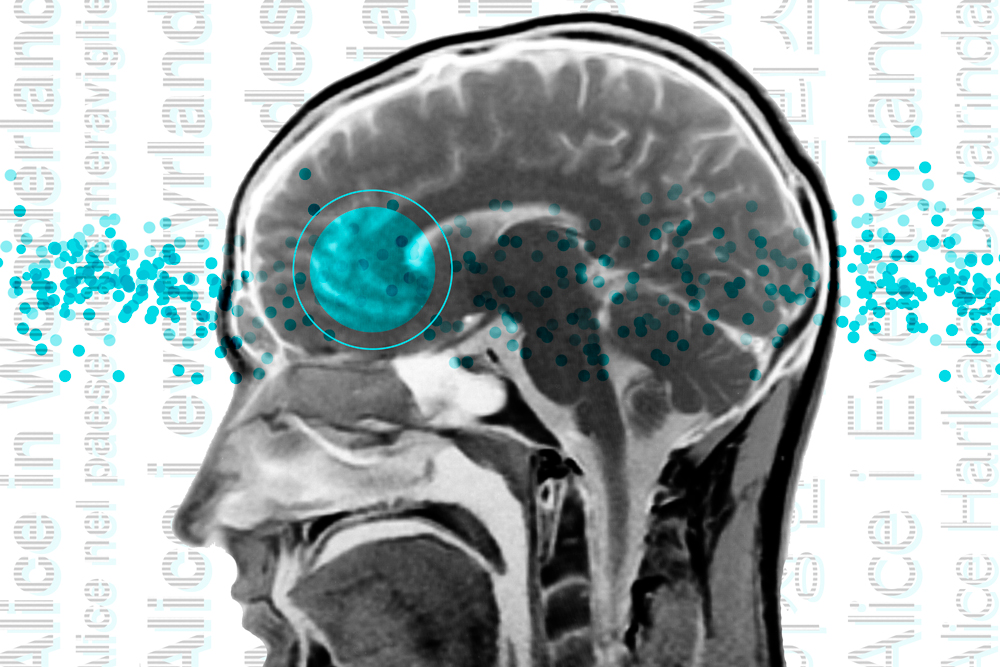

The vast majority of efforts to map the brain’s language network have involved native English speakers. Now, studying brain scans of speakers of 45 different languages, neuroscientists have found this network appears essentially the same across languages.

Credit: Christine Daniloff, MIT; stock image